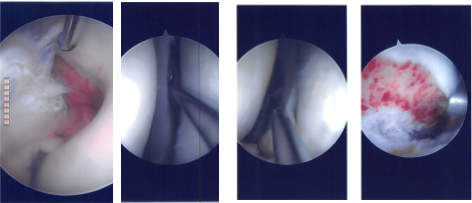

A medical entry portal was also made. There was grade 2 to grade 3 arthritis on the medial femoral condyle, which was cleaned by shaver. There was grade 2 to grade 3 arthritis on the patella, which was cleaned by the shaver, medial as well as lateral meniscus tear. Examination of the intercondylar notch there was 90% tear of the ACL, which was decided to be reconstructed and it was not repairable.

The graft was tightened with a tightrope on either end and found to be in an acceptable position and checked by an arthroscope. The tightropes were tied to each other, and the shuttling suture was removed. Final pictures were taken and saved.

Intraoperative Arthroscopy Images